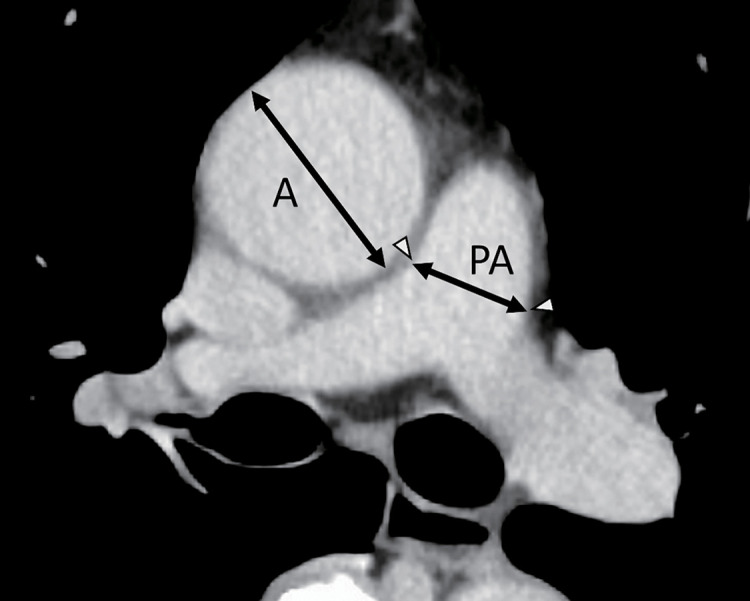

Purpose: The underlying mechanism why segmentectomy has demonstrated the non-inferiority to lobectomy in several randomized trials remains unclear. Computed tomography (CT)-measured pulmonary artery (PA) enlargement reflects PA pressure and predicts the prognosis of certain respiratory diseases. We compared the preoperative and postoperative PA diameter to the ascending aorta diameter (PA/A) ratio, investigating its impact on right ventricular function in lung resection.

Methods: This retrospective study was conducted in patients with lower-lobe lung tumors who underwent anatomical lung resection between 2017 and 2022. The PA diameter at the bifurcation and the ascending aorta diameter at the same CT image slice were measured preoperatively and postoperatively. We calculated the enlargement of PA/A ratio (PA/A change) and compared lobectomy and segmentectomy.